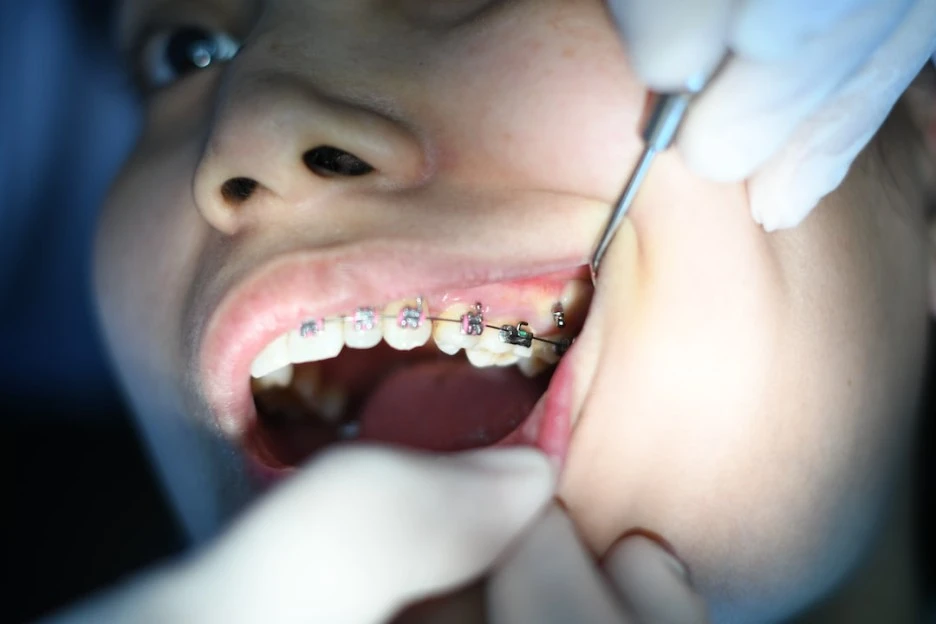

X-ray 사진을 대충 보고 마취 주사를 놓은 뒤(마취 주사는 또 얼마나 따가운지) 스케일링부터 하러 갔다. 동물병원의 경우 스케일링할 때 동물이 절대 가만히 있지 않으므로 전신마취를 하는데 사람은 그렇게 하지 않아서 참 편한 것 같다. 그리고 덜 위험해서 편한 것 같다. 또 요즘은 무통 가글인지 뭔지는 몰라도 그걸 1분간 가글하고 스케일링하면 확실히 시린 느낌이 덜 든다고 하니 세상 참 좋아진 것 같다. 그렇게 스케일링을 간단하게 끝내고 발치하러 체어에 앉았다.

그렇게 살짝 긴장된 마음으로 체어에 앉아있은지 5분 뒤, 원장님이 오시더니 수술 시작하였다. 먼저 우측 상악 사랑니 었다. 메스로 좀 어떻게 해보시더니 나의 사랑니를 금방 발견하시고 나의 사랑니를 힘으로 뜯어내셨다. 마취 덕에 아프지도 않았다. 또 뼈에 붙어서 좀 난도가 있다고 했는데 금방 뜯어버렸다.(뜯어버렸다는 표현이 가장 정확하다.) 금방 끝난 건 좋았는데 나의 멀쩡한 치아를 뜯어내는 그 느낌이 썩 좋지만은 않았다. 메스로 나의 잇몸을 자르고 치과 드릴로 나의 뼈를 깎으며 매복 사랑니에 접근했다. 여기도 사랑니가 단단하게 매복해 있었는지는 몰라도 원장님이 엄청난 힘을 주면서 뜯어내었다. 그 바람에 내 얼굴이 중간중간에 돌아가고 그랬는데(미용실처럼 머리에 힘 빼고 가만히 있으면 되는 줄 알았다.) 그때마다 나의 얼굴을 고정시켜달라고 하셨다. 하지만 원장님의 힘이 세신걸... 그렇게 총 5분간의 수술 끝에 나의 사랑니 발치는 끝났다. 끝나자마자 나의 오른쪽 뺨은 심하게 부어있었다.